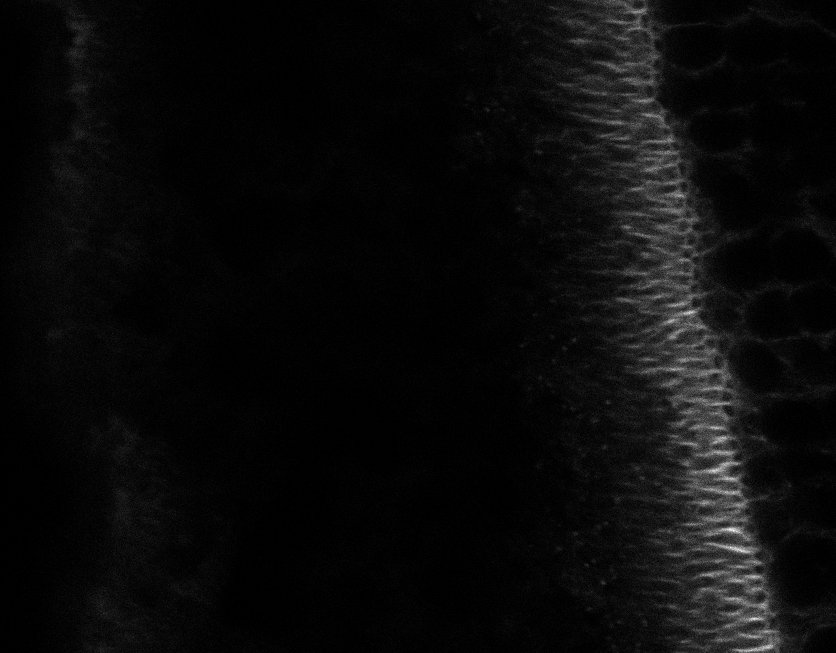

Healthy Choroid

Unhealthy Choroid